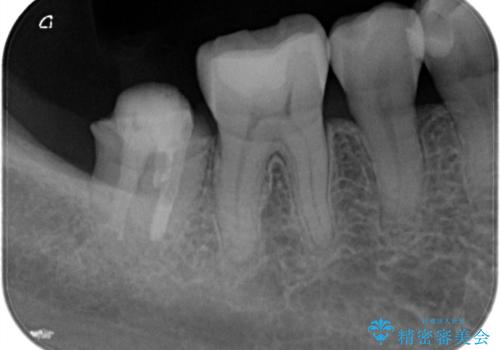

- 他院で治療した被せ物が取れたを主訴に来院された患者様です。被せものが外れた隣の歯もプラスチックの詰め物の劣化や歯に亀裂があったためオールセラミッククランで治療を行いました。

昔詰めたプラスチックの詰め物の範囲が大きいのと破折のリスクや強度の担保のためインレーではなくクラウンで治療を行いました。